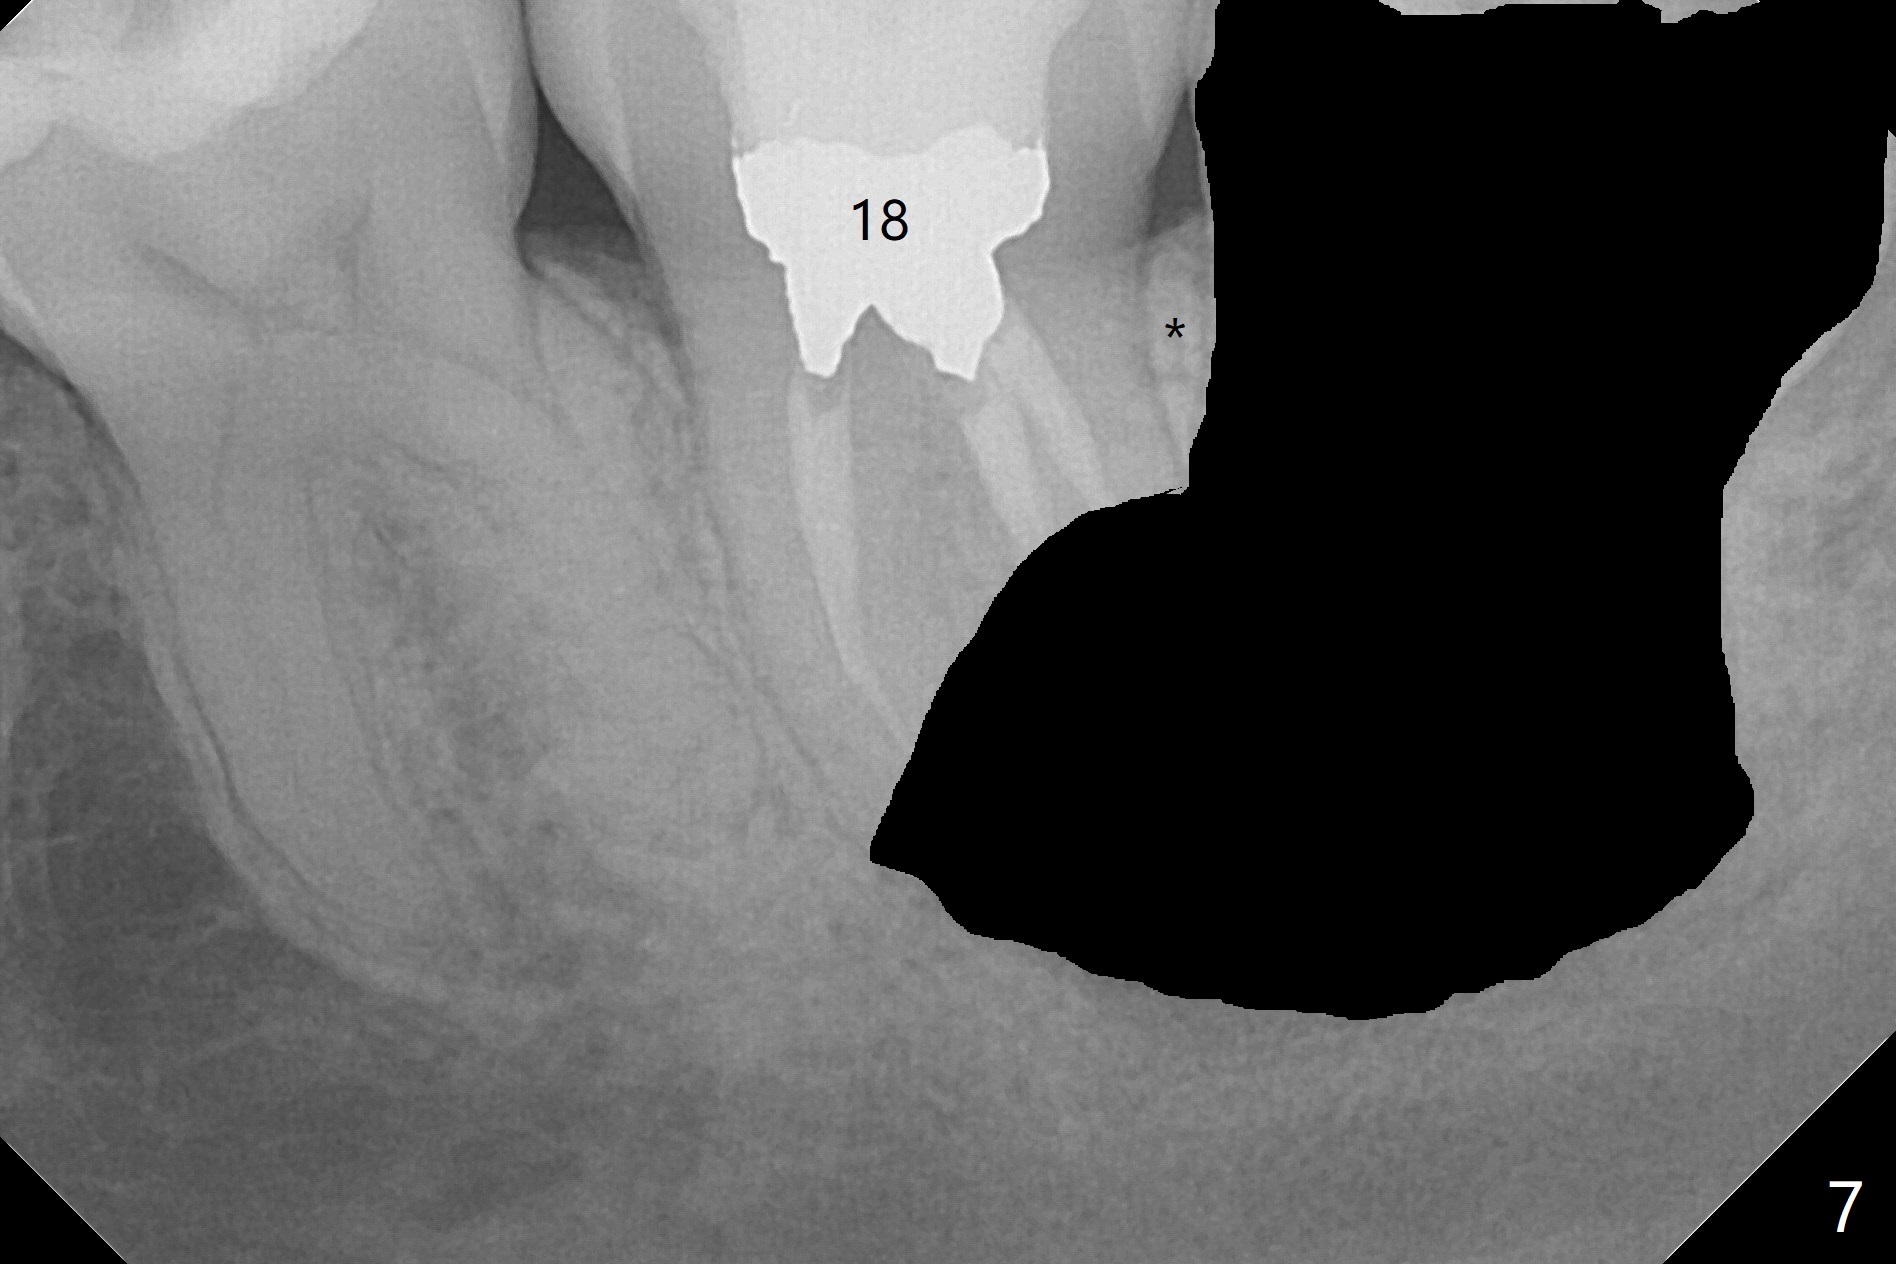

A 37-year-old woman requests extraction of the 3rd molars and orthodontic retreatment (Fig.1). Since the bone between #17 and 18 is thin and short (Fig.2 black *), bone graft is needed after #17 extraction. But the apical infection at #18 (Fig.2 white *) may affect graft survival. The patient agrees to have RCT retreatment done (Fig.3 white curved lines) before extraction (black area). The apical granulation tissue can be removed (Fig.4 red area) prior to bone graft (Augma). The latter will be also placed at #17 as a control. After endodontic consultation, the patient does not want RCT retreatment. She would like to have the 3rd molars extracted first and #18 removed if needed. After #17 extraction (Fig.5), apicoectomy will be performed at #18 (Fig.6 (white outline: surgical bur, use non-torque handpiece)). Following curettage of the apical lesion at #18 (Fig.7), bone graft will be placed (Fig.8 red circles). In fact the patient insists upon #1, 16, 17, and 32 extraction. After extraction, allograft (Fig.9 A (Ossogen, Mineralized Cort/Can (30%/70%), .25-1.0 mm) is placed in the mesioapical of the sockets of #17 and 32, while Osteogen Plug (O) and BioXclude in the distocoronal one (4-0 PGA suture). There is minimal bone between the 2nd and 3rd molars (black arrowheads). The allograft is intentionally pushed into #18 apical defect after enucleation (white arrowhead). The sockets are slightly open, although sutures are in place 2 weeks postop (Fig.10,11). It is unknown whether the bone graft is partially dislodged or not.